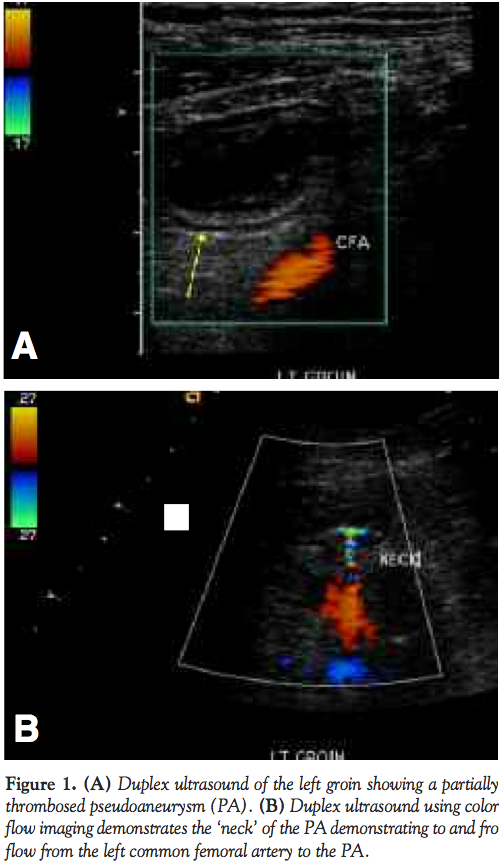

A 36-year-old previously healthy Caucasian woman with longstanding history of tachypalpitations underwent electrophysiological study and AV node re-entry tachycardia (AVNRT) ablation using the left femoral vein approach. Two large-gauge 8 and 10 Fr sheaths were used during the procedure. Her immediate postprocedure course was uneventful. She presented one month later complaining of numbness and tingling in her left foot, with local edema and mild groin discomfort. Pedal pulses were intact and no obvious abnormality was noted on examination of the foot. Lower extremity duplex scan revealed a left common femoral artery pseudoaneurysm (2.2 x 2.3 cm) that had almost completely thrombosed, with a small amount of residual to-and-fro flow (Figures 1A and 1B). It was decided to conservatively manage the pseudoaneurysm, expected to spontaneously thrombose. A few days later the patient presented to the office with complaints of worsening pain in her left leg and foot, which was elicited by even light touch, as well as continued localized swelling and cold sensation. On examination the patient’s foot showed significant coolness, mottling of the skin most notable over the 3rd and 4th toes, mild edema, and normally palpable dorsalis pedis and posterior tibial pulses. We suspected distal embolization from the known femoral pseudoaneurysm. However, repeat duplex scan showed that the pseudoaneurysm had completely thrombosed with normal flow in the common and superficial femoral arteries (SFA) as well as the infragenicular arteries. The patient was started on aspirin and clopidogrel.